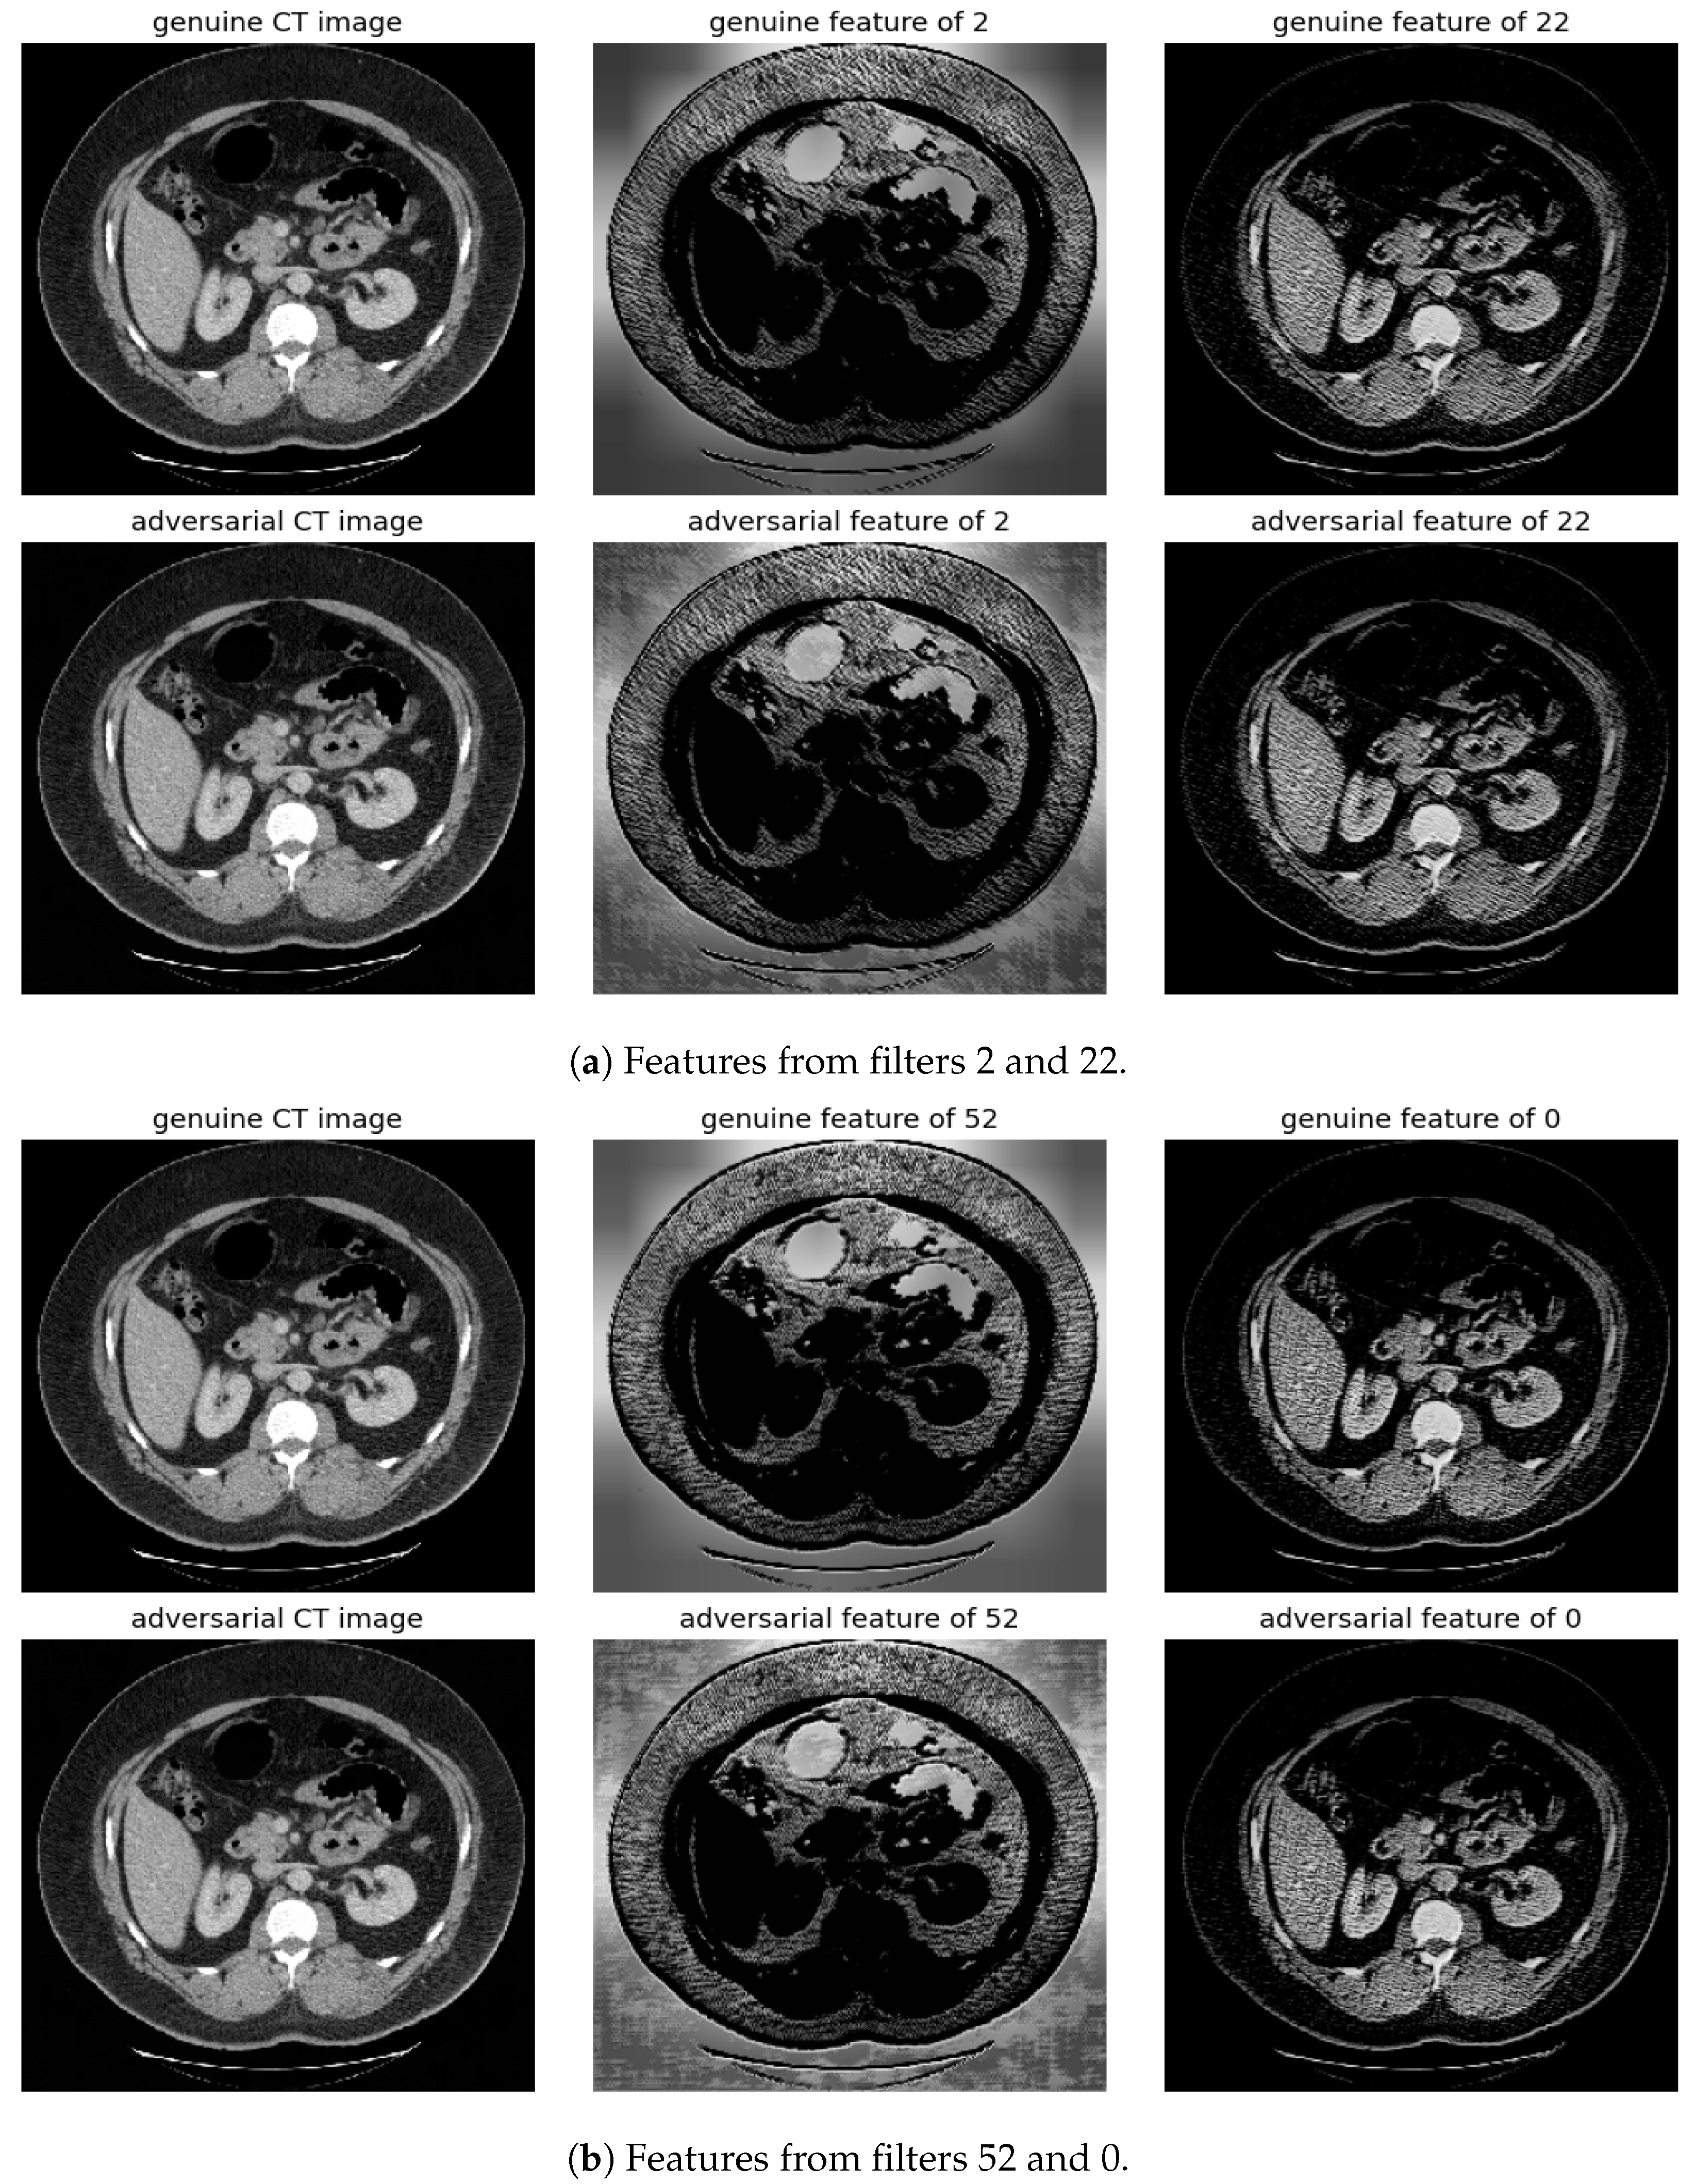

The significance of features associated with the most and least distinctive filters, specifically filter number 2 and filter number 22, is additionally examined. This analysis is conducted across FGSM, BIM, and SMIA for scenarios involving an epsilon of 0.01 and five iterations, excluding FGSM, as illustrated in Figure 7. The evaluation of feature importance is based on the mean decrease in impurity, a method used to assess how dependent variables impact prediction error in random forests [20]. The top 1% of features are presented according to their importance values. As indicated in the figure, the most distinctive feature predominantly concentrates on the background rather than the body, thus enabling easier distinction of adversarial samples from genuine ones. In contrast, the least distinctive feature primarily focuses on the structures surrounding the vertebrae, which may complicate the detection of attacks.

Figure 7.

Visualization of the top 1% of important features from classifiers trained using (a) the distinctive filter number 2 and (b) other than the distinctive filter number 22. These features are derived using the mean decrease in impurity from a random forest classifier for CT segmentation model.

Randomly selected genuine CT samples, alongside their adversarial versions, are displayed in Figure 9, Figure 10 and Figure 11. The adversarial samples were generated using FGSM, BIM, and SMIA attack methods, each with an epsilon of 0.01. While BIM and SMIA used 5 iterations, FGSM did not. These samples represent the most challenging scenarios for human visual detection. Despite the modest epsilon value, as indicated in Table 3, the adversarial attacks have a subtle but pronounced effect. Such slight modifications can lead to major diagnostic inaccuracies potentially impacting patient care.

Figure 9.

Visualization under FGSM Attack: Comparison of features from the first layer between genuine and adversarial samples for the most sensitive (filters 2 and 52) and least sensitive (filters 22 and 0) filters.

To address this, histogram equalization as feature post-processing is applied. The visual representations underscore that while genuine and adversarial samples might appear similar to the naked eye, post-processing brings forth distinct feature differences when employing the most sensitive filters from 2 and 52. Perturbations, especially noticeable in the background of the adversarial samples, are frequently highlighted by these filters. Conversely, features processed with filters from 22 and 0, deemed less sensitive in prior analyses, fail to offer a stark visual contrast.